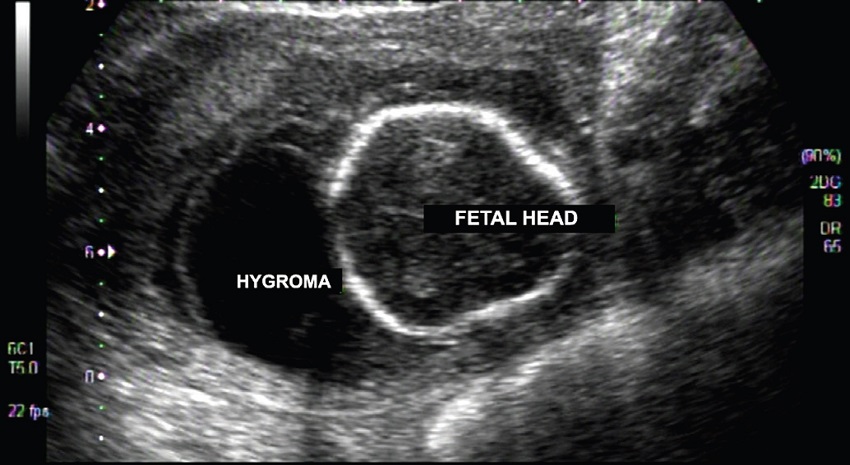

The aim of our study was to report a fetus with Turner syndrome (TS) diagnosed by karyotype from cystic hygroma (CH) fluid, emphasizing the applications and importance of this procedure. A 38-year-old healthy pregnant woman was in her third pregnancy and had a history of two previous miscarriages (all occurred during the first trimester). There was no family history of birth defects or genetic disorders. First-trimester screening revealed an increased nuchal translucency measurement (7 mm), cervical cystic hygroma and head and trunk subcutaneous edema. Ascites was also noted later. There was oligohydramnios, which prevented the execution of amniocentesis. Therefore, at 18 weeks of pregnancy, a puncture of the CH was held for fetal karyotyping, following a long-term culture. Chromosomal analysis showed a X-chromosome monosomy - 45,X[21], consistent with TS. At 21 weeks, there was no fetal heartbeat and spontaneous elimination of the fetus occurred two days later.

The use of CH fluid, obtained through direct hygroma puncture, can be used as an alternative procedure2. Fetal CH is characterized by single or multiple lymphatic congenital cysts and is often found associated with TS3. The procedure is similar to amniocentesis and has low complication rate. If the CH is multiloculated, it is possible to puncture and analyze different regions (especially due to the possibility of mosaicism)4. The karyotype is performed through lymphocyte culture from cystic cells that has a mitotic index and metaphases quality compatible with a blood lymphocyte culture. The karyotype test results using CH puncture are obtained in four days, while by amniocentesis they range from 14-24 days5 (Figures 1 and 2).